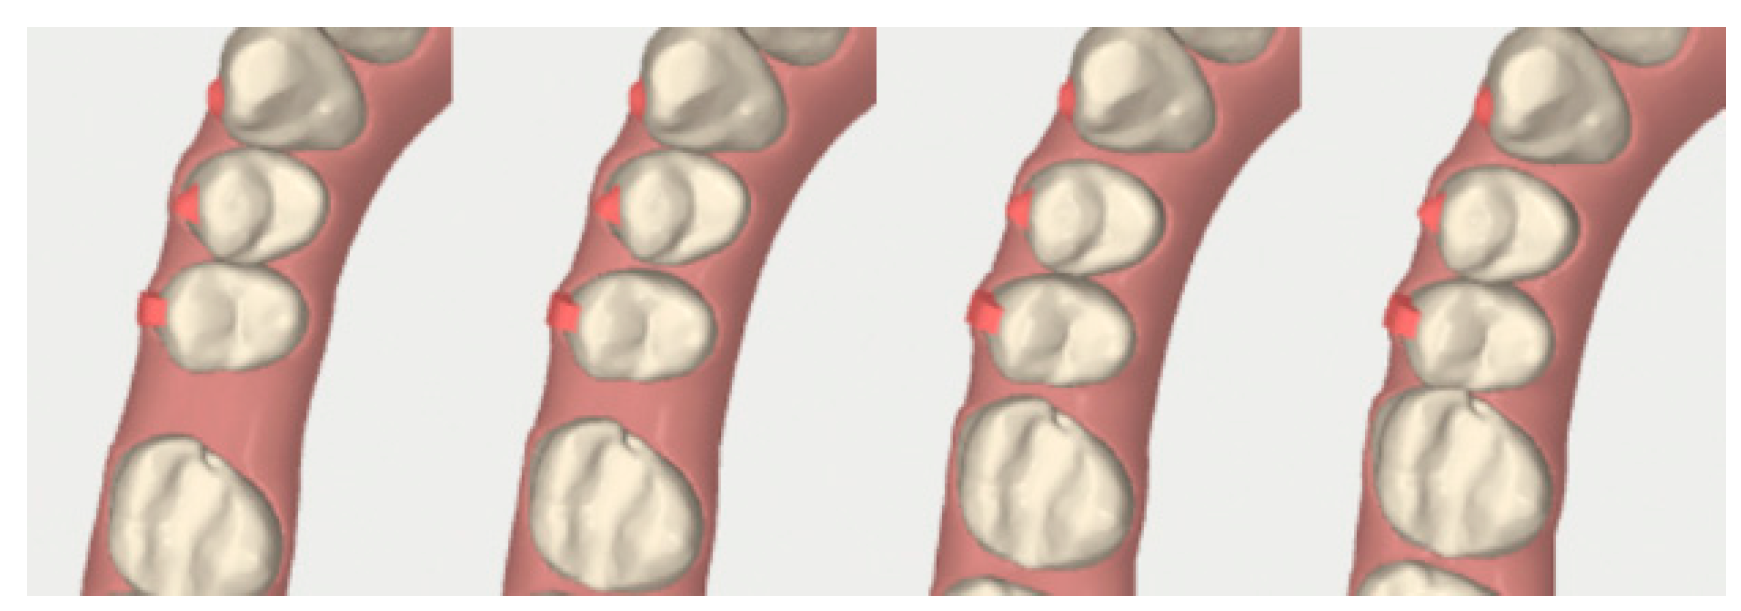

2.3.1. Example—Anterior Open-bite

2.3.2. Example 2—Extraction Space Closure